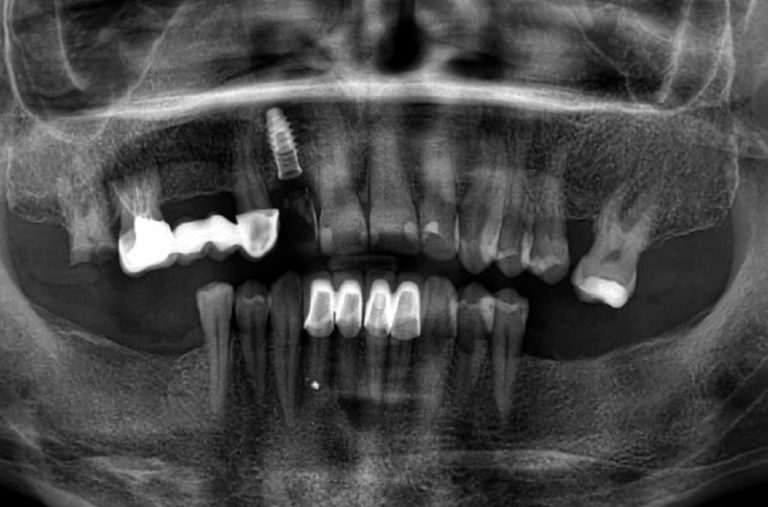

Impianto postestrattivo a carico immediato in sito a valenza estetica e con rarefazione ossea

rarefazióne rarefazione rarefazióne s. f. [der. di rarefare].]. - L'azione del rarefare, il fatto di rarefarsi; in partic., il fenomeno fisico per cui un corpo aeriforme aumenta di volume, conservando intatto il suo [.] peso: continua rarefazione d'esse sostanze, le quali dilatandosi, e perciò ricercando sempre spazii maggiori, fanno forza contro al loro contenente (Galilei); r. di.. Rarefazione ossea denti: cosa sapere. Se si soffre di rarefazione ossea per via della parodontite è importante cercare di correre ai ripari per tempo. La parodontite può essere curata efficacemente solo con un intervento parodontale, un vero e proprio trattamento chirurgico mediante il quale vengono rimossi tutti i batteri che si trovano al.